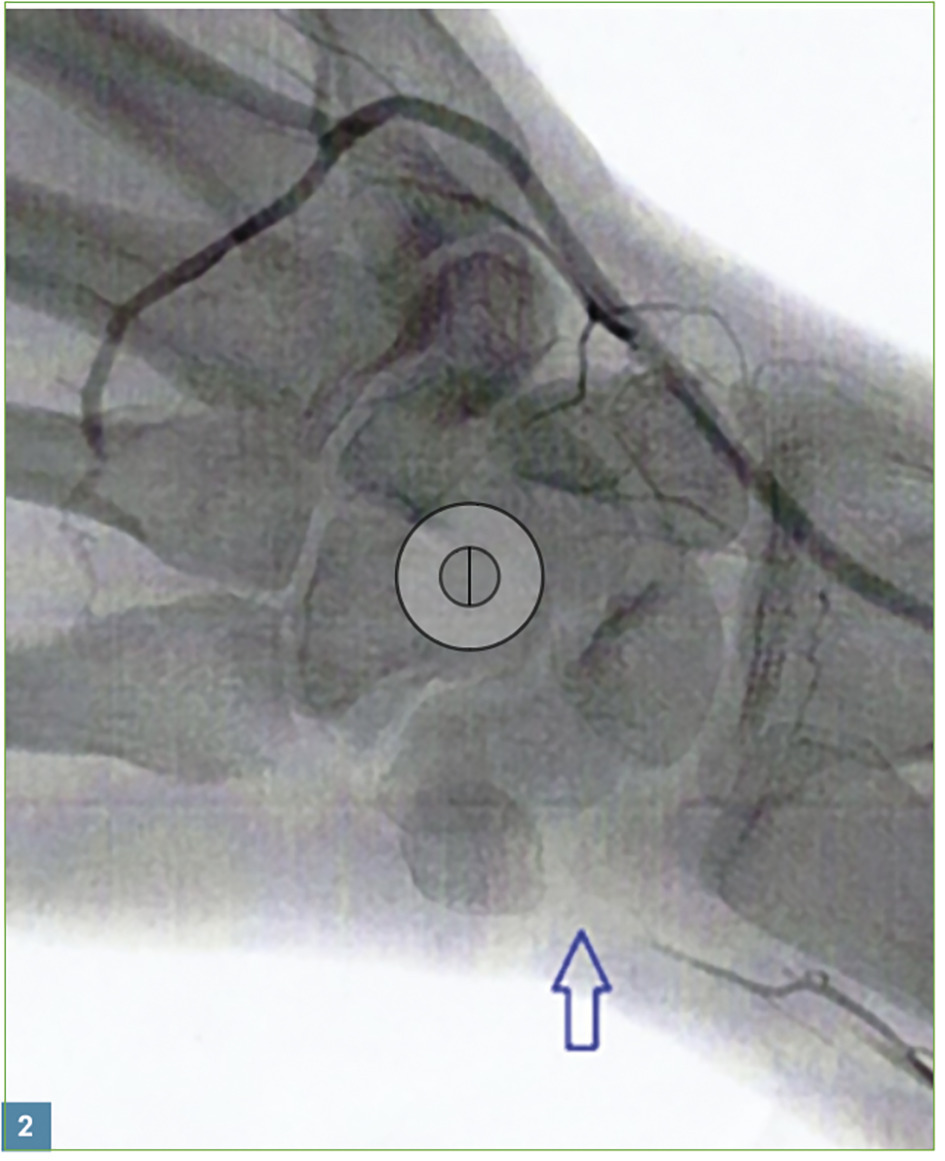

Toutefois, chez ce patient, l’atteinte est unilatérale (fig. 1 ). L’examen montre également une décoloration des 3 derniers doigts de la main dominante. Le test d’Allen est positif (on comprime les artères radiale et ulnaire au niveau du poignet, et on observe la durée de recoloration après avoir relâché la pression sur l’artère ulnaire). Ces signes évoquent un syndrome du marteau hypothénar. En cause, les microtraumatismes répétitifs liés au « passe-temps » de Léo (il est droitier).

Toutefois, chez ce patient, l’atteinte est unilatérale (